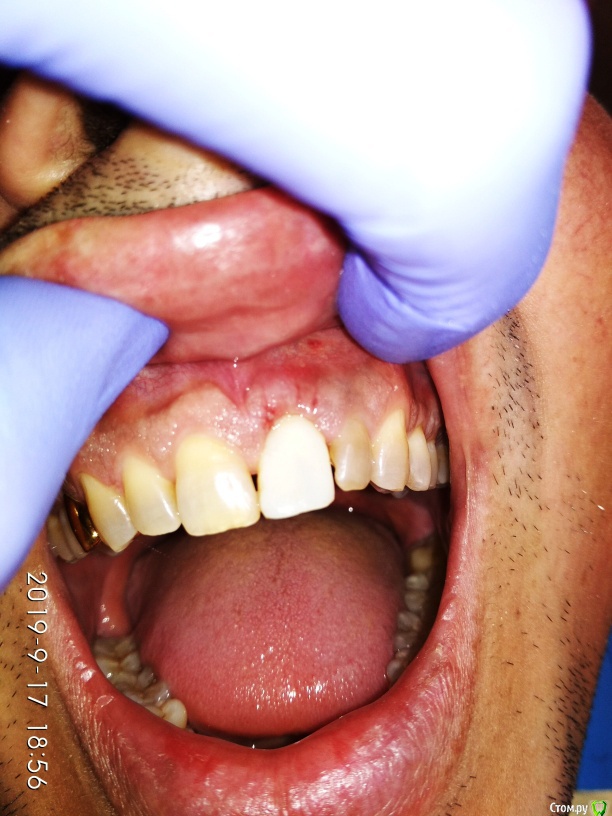

Дмитрий М Опубликовано 25 сентября, 2019 Поделиться Опубликовано 25 сентября, 2019 Пуциент 43г. перелом 21 зуба пациент без эстетических притязаний, совсем. главное, чтобы было дешево )))воксап- удаление - щит- имплантация- изготовление временной- фиксация Ссылка на комментарий

Дмитрий М Опубликовано 18 октября, 2019 Автор Поделиться Опубликовано 18 октября, 2019 Времяшку по ключу делали? Если да, то чем и как изолировали лунку от пластмассы в нем?Да по ключу. вкрутил вр.абат. сделал "юбку" из жидкотекучего, открутил, доработал в руках, получилось плотно герметично по контуру десны Ссылка на комментарий